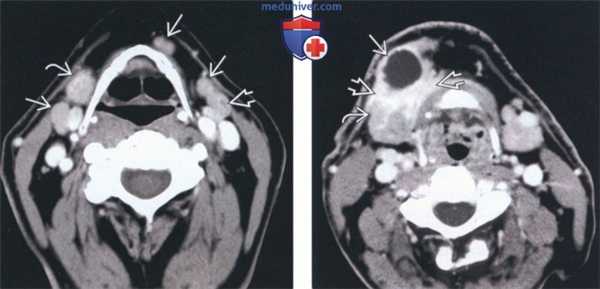

(Слева) На аксиальной КТ с КУ у пациента с плоскоклеточным раком (ПКР) нижней губы визуализируется единственный патологически измененный (с едва различимым гиподенсным центром) лимфоузел ПНП IB уровня, лежащий снаружи от переднею брюшка двубрюшной мышцы.

(Справа) На аксиальной КТ с КУ надподъязычной области шеи определяется увеличенный округлый лимфоузел IB уровня, накапливающий контраст (метастаз). Увеличенная левая поднижнечелюстная железа (ПНЖ) накапливает контраст, проток в воротах железы расширен. ПКР передних отделов дна полости рта (не визуализируется) приводит к обструкции протока поднижнечелюсгной железы. (Слева) На аксиальной КТ с КУ у пациента с первичным ПКР дна передних отделов полости рта визуализируются множественные лимфоузлы уровня IB. Лимфоузлы накапливают контраст но не все отвечают КТ критериям злокачественности. Лишь два лимфоузла отвечают критериям: один справа на основании размера >1,5 см и один слева на основании центральной гиподенсной области.

(Справа) На аксиальной КТ с КУ у пациента с ПКР наружного края языка определяется большое кистозное образование лимфоузла ПНП IB уровня. Контрастирующиеся края лимфоузла неотделимы от окружающих тканей, что позволяет предположить экстракапсулярное распространение. ПНЖ окружена опухолью.

(Слева) КТ с КУ, аксиальная проекция. Пациент с плоскоклеточным раком нижней губы. Виден один измененный узел (центр низкой плотности) поднижнечелютного пространства. Узел расположен латеральнее переднего брюшка двубрюшной мышцы (уровень IB).

(Справа) КТ с КУ, аксиальный срез в над-подъязычной области шеи. Увеличенный, округлый, накапливающий контраст лимфоузел уровня IB. Левая поднижнечелюстная железа увеличена, накапливает контраст. Ее проток расширен. Опухоль передней части дна полости рта вызывала сдавливание поднижнечелюстного протока. (Слева) КТ с КУ, аксиальная проекция, пациент с ПКР дна полости рта и множественными увеличенными лимфоузлами уровня IB. Некоторые из них накапливают контраст, но не все являются злокачественными по КТ-критериям. Два лимфоузла соответствуют критериям злокачественности: один справа (> 1,5 см), другой слева (центральный участок пониженной плотности).

(Справа) КТ с КУ, аксиальная проекция. Крупный кистозный лимфоузел уровня IB у пациента с плоскоклеточным раком боковой поверхности языка. Края лимфоузла неотличимы от окружающих тканей, что говорит о внекапсулярном распространении. Поднижнечелюстная железа окружена опухолью.